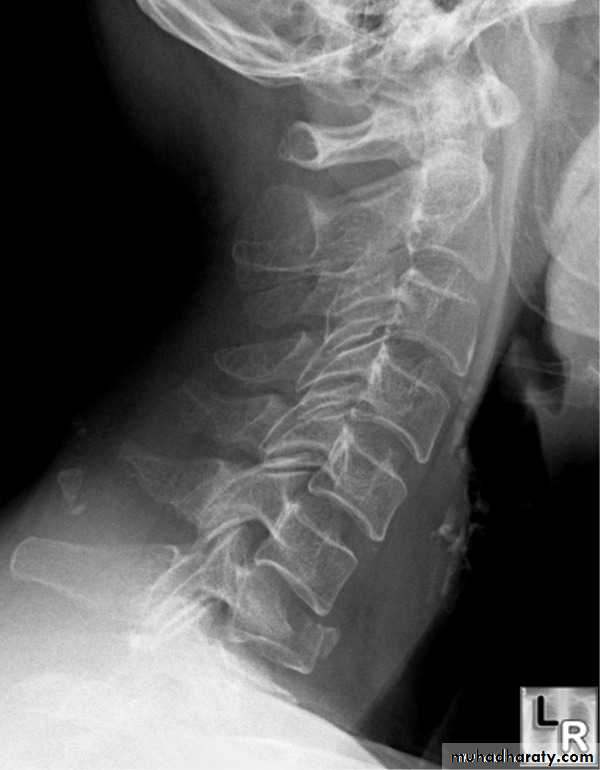

Spine injuries

Cervical classifications

extension subluxation

flexion subluxation

Flexion and flexion-rotation injuries

frcature spine and peripheral nerve

are common:

flexion alone tends to a wedge compression fracture .

whereas combined flexion and rotation cause subluxation ,

dislocation or fracture-disIocation.

A flexion or flexion-rotation force may also cause massive displacement of an intervertebral disc, without bone injury

A hyperextension

force may fracture the neural arch, especially of the atlas

Or fracture the dens (odontoid process) of the axis.

hyperextension may rupture the anterior longitudinal ligament and the

anulus fibrosus, forcing the vertebral bodies apart anteriorly (extension

subluxation) .

DIAGNOSISX RAY

Anterio posterior X ray radiograph.lateral radiographs with the head in flexion and extension may revealinstability that is not shown in the routine lateral film.

oblique views

at 45° are especially helpful

a special projection

through the open mouth.

Computed tomography (CT)

and magnetic resonance imaging (MRI).